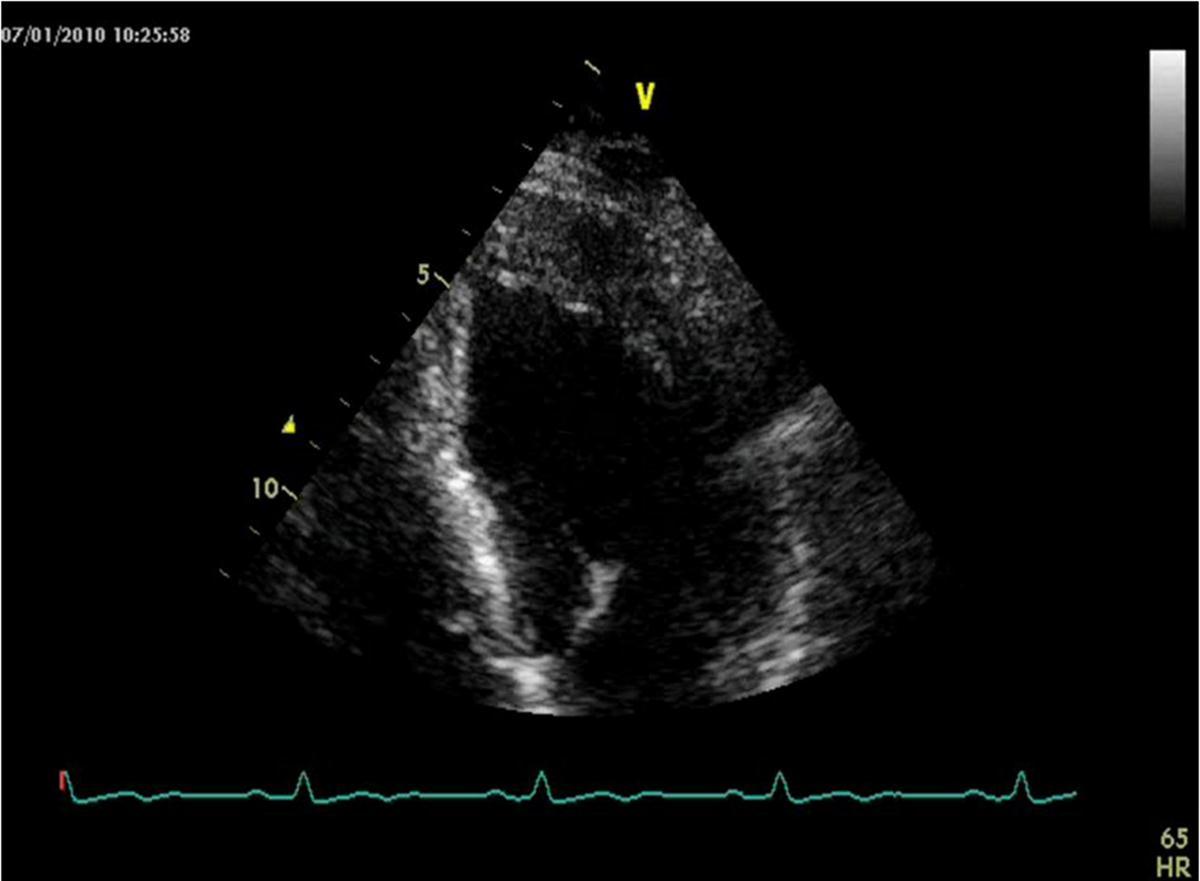

He was asymptomatic, in good general conditions, blood pressure 120/80 mmHg, no murmurs. The electrocardiogram showed sinus bradycardia (55 bpm) and left ventricular hypertrophy signs (deep and symmetric negative T waves in DI, aVL, V2 till V6). Echocardiogram (VIVID 7, 2-4 MHz probe) showed non classical apical hypertrophic cardiomyopathy (Figure 2), localized at anterior, lateral and posterior apex (septum was preserved), with no obliteration of apical cavity. By mean of color-Doppler evaluation, we observed multiple and thin color flows from LAD draining into apical region. Pulse-wave Doppler temporization was exclusively diastolic (Figure 3). Stress echocardiography with accelerate dipyridamole resulted negative for inducible ischemia and no variation in fistula flow was detectable. Inguinal hernia intervention was safely performed and the patient was advised to undergo periodical cardiologic controls.

Figure 3.Echo-color Doppler evalutation of left anterior descending artery fistula draining in left ventricular cavity

Echo-color Doppler evalutation of left anterior descending artery fistula draining in left ventricular cavity